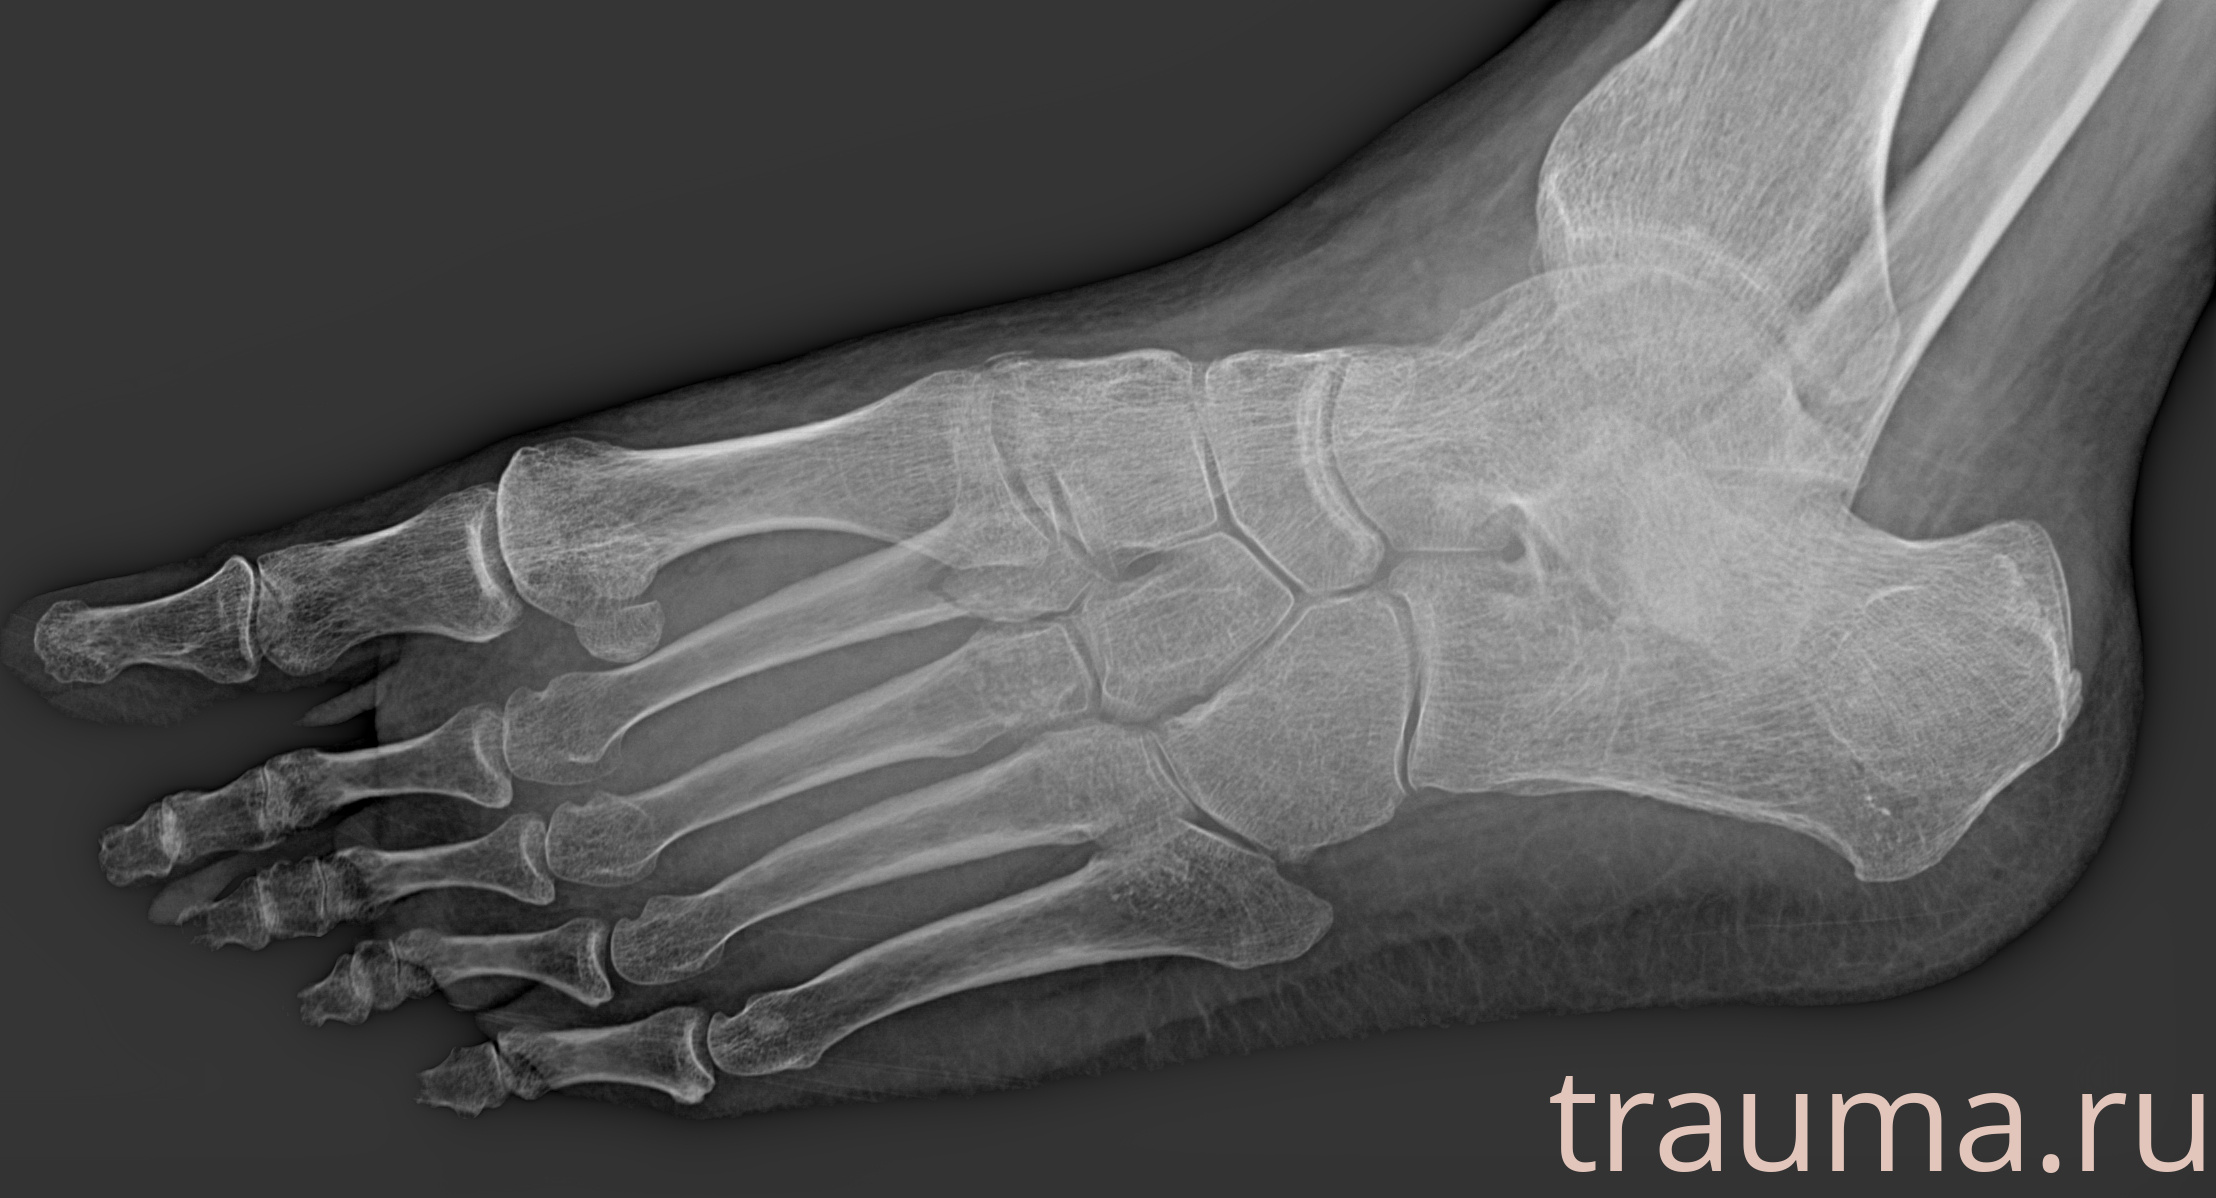

Рентген на дому: по вашему адресу приезжает врач-рентгенолог, травматолог-ортопед с мобильным рентгеновским аппаратом, проводит диагностику травмы или заболевания, делает необходимые рентгенограммы, дает рекомендации по дальнейшему лечению. Получить качественные снимки в домашних условиях возможно благодаря уникальной методике, разработанной МосРентген Центром для института  Склифосовского